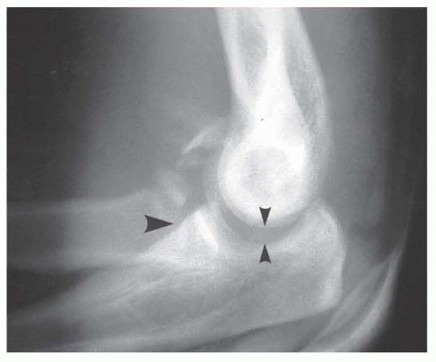

Meticulous preoperative planning is the cornerstone of a successful surgical outcome in elbow fracture-dislocations. High-quality plain radiographs in the anteroposterior (AP) and lateral planes must be obtained before and after any closed reduction attempts. However, cast material and overlapping osseous structures often obscure critical bony detail. Therefore, computed tomography (CT) scanning with thin cuts, multiplanar reformatted images, and three-dimensional (3-D) reconstructions is considered the gold standard and is mandatory for surgical planning. 3-D CT allows the surgeon to precisely understand the size, comminution, and spatial orientation of the coronoid and radial head fragments, dictating whether primary osteosynthesis is feasible or if arthroplasty will be required.

Coronoid fractures are equally critical to evaluate, as the coronoid provides the anterior buttress preventing posterior subluxation of the ulna. These have been traditionally classified by Regan and Morrey: Type I (tip avulsions, often representing capsular avulsions rather than true osseous stabilizers), Type II (less than 50% of the coronoid height), and Type III (more than 50% of the coronoid, often involving the sublime tubercle and MCL insertion). However, modern biomechanical understanding emphasizes the anteromedial facet fracture, a distinct entity caused by a primary varus force. The medial facet is paramount for varus stability of the elbow. These fractures are inherently unstable and are best treated with open reduction and internal fixation utilizing a medial buttress plate, as failure to recognize and stabilize the anteromedial facet will lead to rapid articular wear and chronic varus instability.

The radial head serves as a crucial secondary stabilizer to valgus stress and posterior translation, particularly when the MCL is compromised. It also functions as a longitudinal stabilizer of the forearm, preventing proximal radius migration. Radial head fractures have been classically described by the Mason classification: Type I (small or marginal fracture with minimal displacement), Type II (marginal fracture with displacement), Type III (comminuted fractures of the head and neck), and Type IV (radial head fracture associated with elbow dislocation—the Johnson modification). In the setting of a fracture-dislocation, the radial head must never be excised without replacement; doing so in the absence of a competent MCL and coronoid will universally lead to catastrophic recurrent instability.